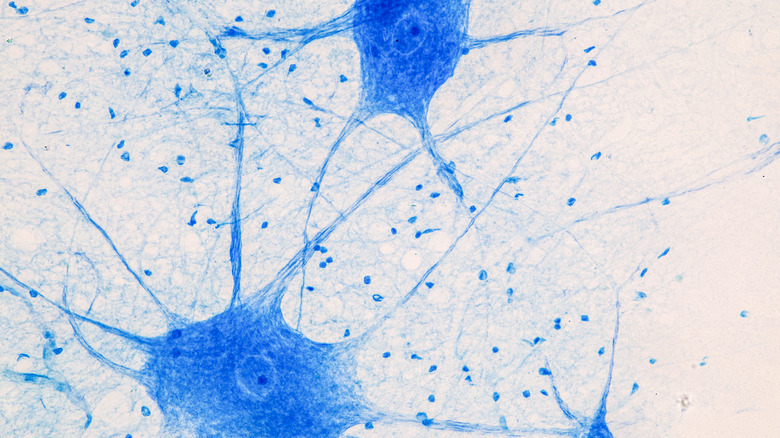

The average human brain has more than 86 billion neurons, most of which we are born with. However, the impressively large numbers don't end there, as each of these neurons can form connections with thousands of others, to form over 100 trillion connections, a class of structures known as synapses.

This area of neuroscience is incredibly recent, and it's creating a new understanding of how these crucial parts of our brain work together. Known as connectomics, it aims to use the latest mapping methods to explore how individual neurons interact with each other, something which understandably takes a long time. At Harvard, however, researchers have invented a much faster method for mapping the neurons of the human brain, which, according to an associate professor of neurology at Harvard Medical School, can "capture the whole nervous system of an adult fruit fly in a few months." Though the science of connectomics is still in the very early stages, the progress made in recent years means we could potentially deepen our understanding of neural connections considerably in the coming decades.

Neurons are the nerve cells found throughout the body that transmit information from one place to another. There are around 100 billion neurons in our body, and unlike many of the cells in the rest of the body, they can last the entire time that we are alive.

Most neurons are created before we even take our first breath, as the process begins in the second month of pregnancy and continues until birth.  Almost all of the neurons you need for your entire life are present when you are born, with a small number being created in early childhood. At death, the neurons will then die too, but the most recent research suggests that neurons are capable of surviving and functioning much longer than the average lifespan of the body housing them.

Lorenzo Magrassi is a neurosurgeon at the University of Pavia, and his research involving the neurons of mice and rats has convinced him that the longevity of neurons is restricted only by the lifespan of the animal in question. "Neurons do not have a fixed lifespan," he said. "They may survive forever. It's the body that contains them that dies" (via National Geographic). While the research into neurons still has much to reveal, the idea that neurons do not necessarily have to die as a result of old age could be critical in future treatments from cognitive disorders.